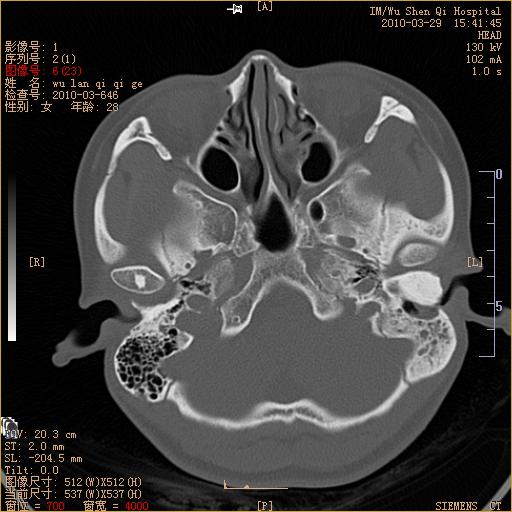

标题: CT25398:女,左耳流脓两年余,带有异物 [打印本页]

标题: CT25398:女,左耳流脓两年余,带有异物

左侧中耳乳突炎,不排除胆脂瘤形成。

左侧中耳乳突炎,胆脂瘤形成。

左侧中耳乳突炎,不排除胆脂瘤形成

1)左侧慢性中耳乳突炎并肉芽肿(或胆脂瘤)形成。2)考虑左侧颞骨慢性炎症伴骨质增生硬化,不排除骨纤。